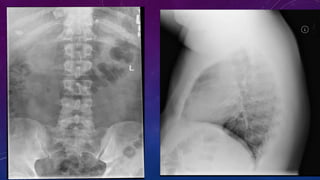

• Multiple pelvic phleboliths.

• Small well-defined round osseous lesions in the left

side of the abdomen, adjacent to midline represent

calcified lymph node in the para-aortic and left

common iliac groups, also visualized on the

corresponding CT.